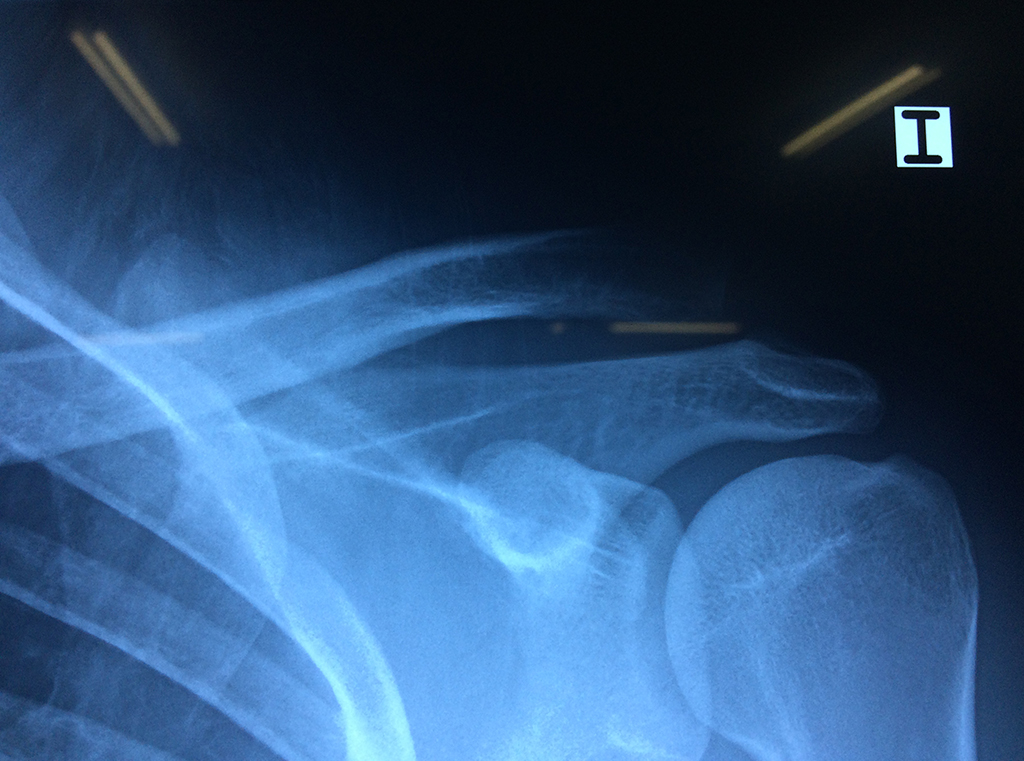

La principal articulación del hombro es la que une la cabeza del húmero con la escápula, recibe el nombre de articulación escapulohumeral y presenta dos superficies articulares, una de ellas corresponde a la cabeza del humero que tiene forma semiesférica y la otra es la cavidad glenoidea de la escápula, estas superficies están recubiertos por cartílago que permiten un movimiento suave e indoloro.

Varias estructuras transparentes en forma de saco llamadas bolsas serosas, permiten el deslizamiento suave de los diferentes componentes móviles. El hombro es la articulación con mayor amplitud de movimientos del cuerpo humano.